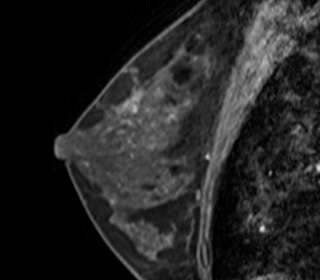

図4 MRI画像

マンモグラフィーや超音波検査で悪性が疑われる場合や、乳がんの拡がりを判断する必要がある時には、精密検査としてMRI検査(要予約)を行います。